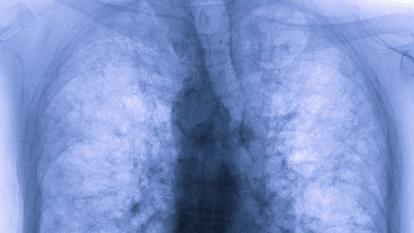

Pr Chantal RAHERISON-SEMJEN. - Oui, on sait que c’est à la fois une infection respiratoire et une maladie des vaisseaux. Au niveau des poumons, il y a des dommages alvéolaires. Les alvéoles sont les petits sacs où se font les échanges respiratoires (l’oxygène rentre et le dioxyde de carbone sort). Dans le Covid-19 il y a une inflammation diffuse avec de l’œdème et, dans certains cas, la multiplication de cellules appelées fibroblastes qui provoquent une fibrose, c’est-à-dire une rigidification de la paroi alvéolaire.